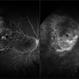

- intraocular gas

- Fundus camera

- POP View of RD repair with air bubbles